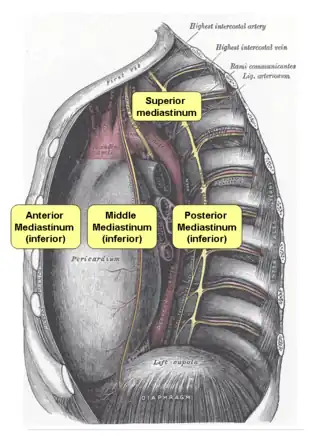

Mediastinum, lateral view. The division between superior and inferior is at the sternal angle. | |

The mediastinum can be divided into an upper (or superior) and lower (or inferior) part:

- The superior mediastinum starts at the superior thoracic aperture and ends at the thoracic plane.

- The inferior mediastinum from this level to the diaphragm. This lower part is subdivided into three regions, all relative to the pericardium – the anterior mediastinum being in front of the pericardium, the middle mediastinum contains the pericardium and its contents, and the posterior mediastinum being behind the pericardium.[6]

Anatomists, surgeons, and clinical radiologists compartmentalize the mediastinum differently. For instance, in the radiological scheme of Felson, there are only three compartments (anterior, middle, and posterior), and the heart is part of the middle (inferior) mediastinum.[7]

Thoracic plane

The transverse thoracic plane, thoracic plane, plane of Louis or plane of Ludwig is an important anatomical plane at the level of the sternal angle and the T4/T5 intervertebral disc.[8][9][10] It serves as an imaginary boundary that separates the superior and inferior mediastinum.[8][9][10]